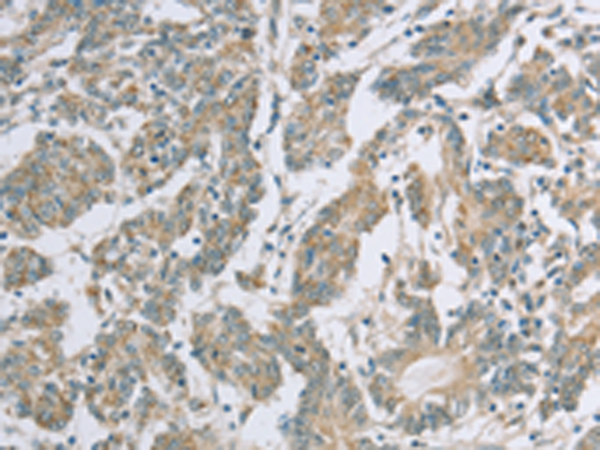

分类: 科研抗体货号: P08287别名: EPDR; UCC1; MERP1; MERP-1应用: WB,IHC反应种属: Human, Mouse, Rat